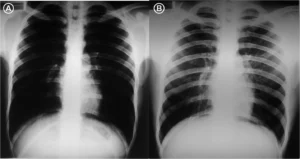

4.1 Consolidación pulmonar (neumonía)

Sustitución del aire alveolar por exudado o células. Se ve como un área radiopaca con broncograma aéreo.

Clave digital: ajustar la “ventana pulmonar” ayuda a delimitar mejor la extensión del infiltrado.

Caso relacionado: Consolidación

4.2 Atelectasia

Significa literalmente pérdida de volumen, en este caso pulmonar. Este es el dato clave, ya que la imagen de la atelectasia es variable, puede ser radiotransparente o radiopaca, y la localización depende del lóbulo o segmento comprometido.

Pero siempre encontrarás los signos de pérdida de volumen. Busca el desplazamiento de la tráquea, la elevación diafragmática o la aproximación de las costillas.